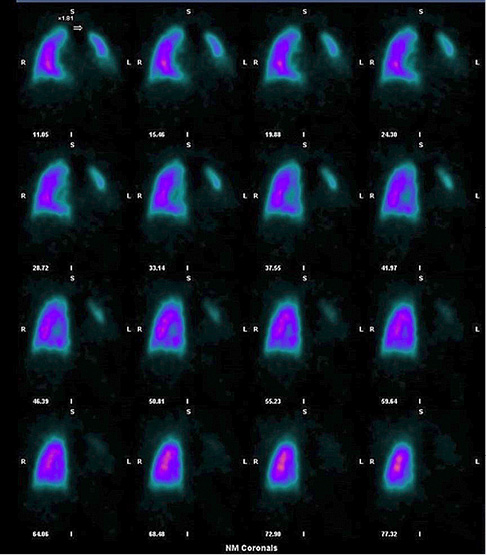

The patient previously suffered from AF which was difficult to control with oral drugs. A successful RFA procedure was performed seven months before the admission, and the sinus rhythm was restored. However, chest computed tomography (CT), performed the next day after RFA, showed a significant narrowing of the left lower pulmonary vein (up to 3.5 mm) (Figure 1A). The patient had only mild symptoms and was treated conservatively.

On admission a chest X-ray showed subtle patchy consolidations in the left lower lobe of the lung (Fi­gure 1B). A chest CT scan showed patchy consolidations, areas of atelectasis of the left lower lobe parenchyma (Figure 1C), and the absence of communication between the left lower pulmonary vein and the left atrium (Figure 1D). A quantitative ventilation/perfusion scan (99mTc-MAA 98MBq) revealed that the left lung was receiving only 15% of the overall lung perfusion with no perfusion to the left lower lobe (Figure 2). Bronchoscopy found striking hyperemia and brisk bleeding to touch of the mid and distal left lower lobe bronchus. Based on instrumental and clinical findings, it was decided to perform balloon angioplasty with further stent implantation. However, the procedure was unsuccessful, due to an invisible lumen or dimple, that can be probed in the vein.

Figure 1. CT scan showing narrowing of the left lower PV (A); chest X-ray with patchy area in the left lower lobe (B); CT scan showing areas of patchy consolidation of the left lower lobe (C), and total occlusion of the left lower PV (D)